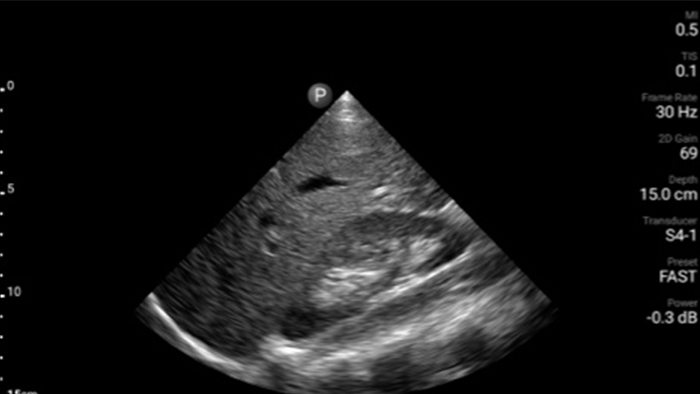

Exceptional ultrasound imaging

Lumify handheld ultrasound offers images that enhance diagnostic confidence.

See more when it counts

Lumify can help you make real-time decisions with more confidence, from assessment to recovery. Reveal the subtle details of an image, uncover enriched tissue definition with multiple angles and much more.

Emergency medicine